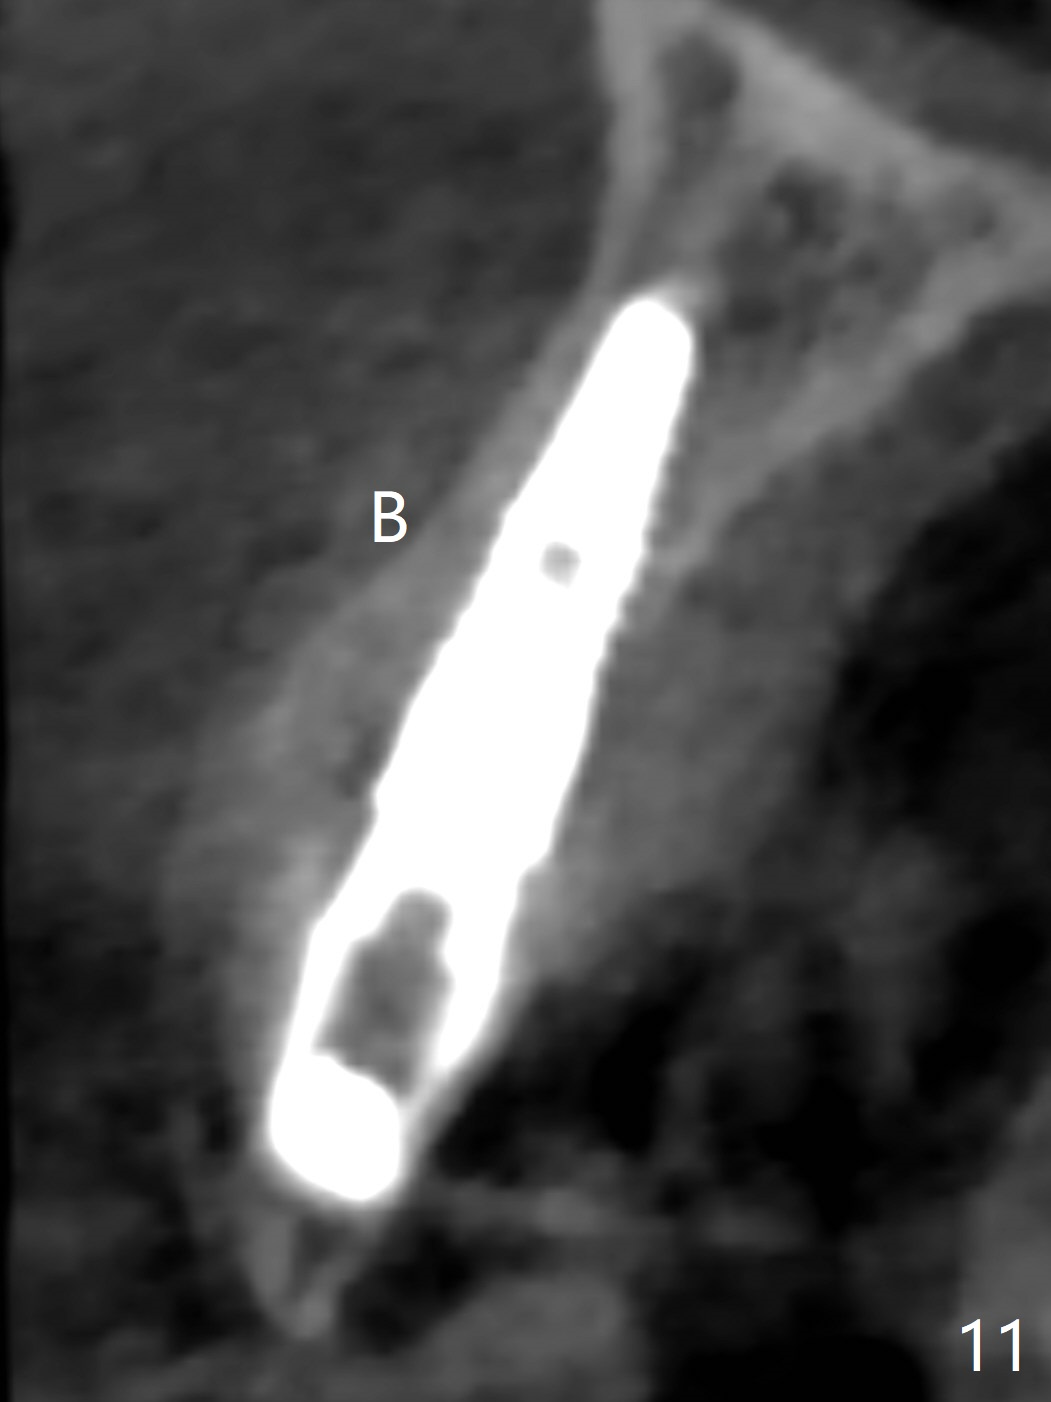

When the patient returns, the crown at #10 has displaced incisally (Fig.1,2 arrow). The initial depth is 15 mm (Fig.3, palatal gingival margin). After a 3.8x12 mm SM implant is placed (Fig.4), allograft is packed in the peri-implant space (*, as compared to Fig.3) and a 3.9x4(3) mm abutment is placed (A). More allograft is placed in the peri-abutment space (Fig.6 *). The existing crown (Fig.4,5 C) is hollowed, relined (R) and used as an immediate provisional (Fig.7-9). The patient is pleased with the appearance of the apically-repositioned provisional (Fig.7 arrow). She returns for impression 3.5 months postop (Fig.10). After change of abutment to 3.9x4(4.5) mm and new provisional, impression is retaken 5 months postop (Fig.11,12). It appears that the implant is palatally placed and a little large for the site (Fig.11 (B: buccal); Fig.12 (^: thin layer of the palatal plate)). If an angled abutment were used, a screw-retained crown might have been feasible. Due to the new provisional, the gingiva looks healthy when a permanent crown is cemented (Fig.13).